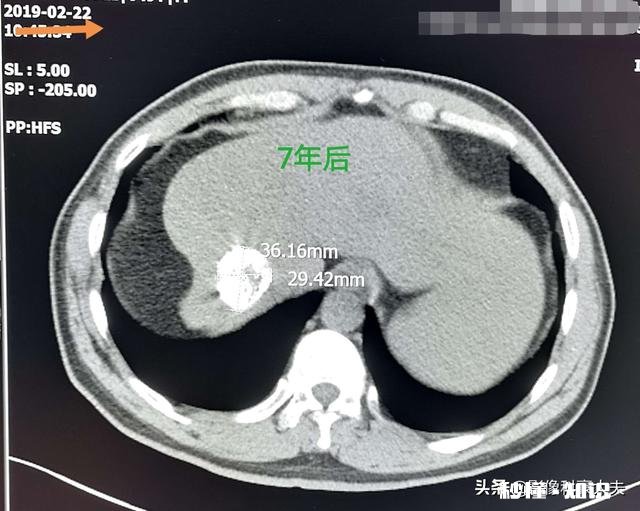

文章插图

这是一位中年男性,有多年乙肝病史 , 查出肝右叶肝癌 。通过介入化疗栓塞术,配合射频消融治疗已经7年了,没有复发!

这是一位62岁老烟民,右肺中叶肺鳞癌,手术切除一年半后复发,在肺门区形成肿块 。通过定点放疗杀灭癌细胞 , 肿块萎缩,目前已经7年多了 。